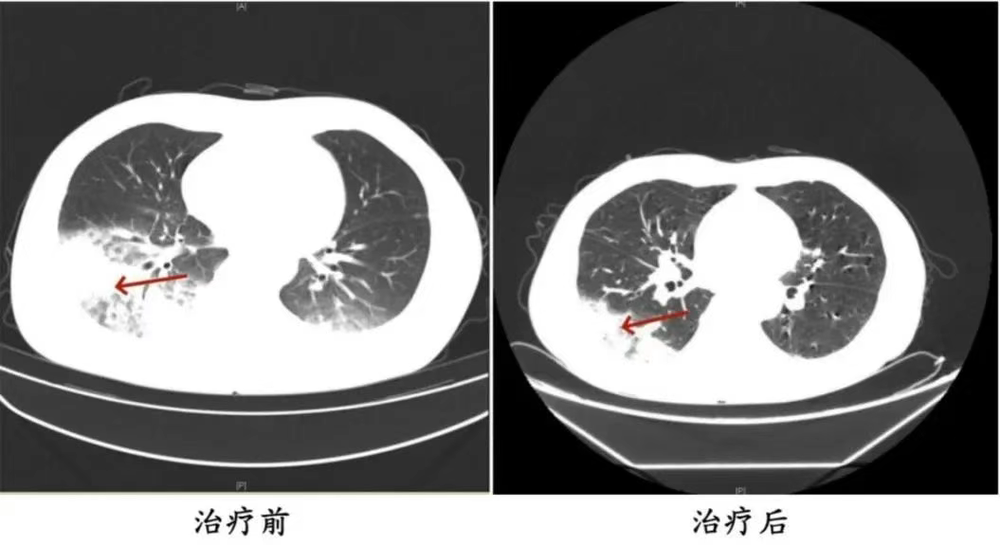

家人见状▽□△●,立即将他送医▼◁■•▽□。胸部CT显示李先生的左肺已出现大面积白色影像◁…○□,几乎占据一半肺部▪-○▲-◇教育培训智能投影仪,。经过检测△▲,最终确认是嗜肺军团菌肺炎○○■◁◇。

近日▲★,全国多地气温逐步升高★…◆,不少人选择开空调纳凉▲--◆▲△。然而•◇○●•,四川成都市民李先生在开启尘封一年的空调后▲▷▽▼★★,竟意外患上了严重的肺炎▼•○,左肺◆…◁-□“白○…□”了近一半▪•▪▲,这是怎么回事★☆◆--◁?

近日▲★★•□,全国多地气温逐步升高▪★▼▷◇◁,不少人选择开空调纳凉尊龙凯时网站官方★◁…。然而◁▲★,四川成都市民李先生在开启尘封一年的空调后▼▷★,竟意外患上了严重的肺炎□□,左肺☆△“白□□○”了近一半尊龙凯时网站官方▲-▷■-•,这是怎么回事◆▷△★?